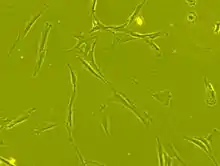

Human bone marrow derived mesenchymal stem cells seen under phase contrast microscope (63 x magnification)

Stem cell transplantation is an important avenue for SCI research: the goal is to replace lost spinal cord cells, allow reconnection in broken neural circuits by regrowing axons, and to create an environment in the tissues that is favorable to growth.[73] A key avenue of SCI research is research on stem cells, which can differentiate into other types of cells—including those lost after SCI.[73] Types of cells being researched for use in SCI include embryonic stem cells, neural stem cells, mesenchymal stem cells, olfactory ensheathing cells, Schwann cells, activated macrophages, and induced pluripotent stem cells.[151] Hundreds of stem cell studies have been done in humans, with promising but inconclusive results.[139] An ongoing Phase 2 trial in 2016 presented data[152] showing that after 90 days, 2 out of 4 subjects had already improved two motor levels and had thus already achieved its endpoint of 2/5 patients improving two levels within 6–12 months. Six-month data is expected in January 2017.[153]